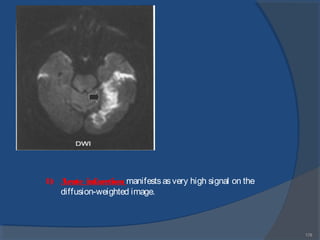

1)Acute infarction manifestsasvery high signal on thediffusion-

weighted image.

1) Acute infarction manifestsasvery high signal on the

diffusion-weighted image.